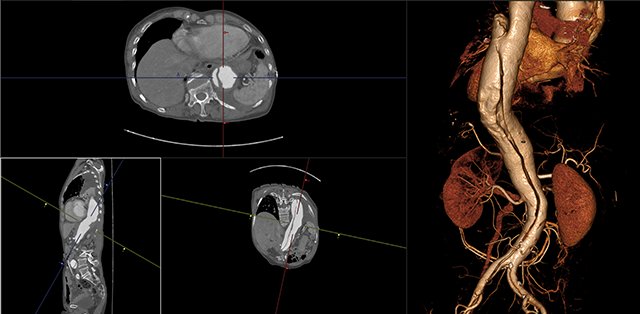

View X-Ray CT & MRI Scans Fast and Easily

FREE and easy to use 3D DICOM Viewer – for surgeons and patient education

Designed for surgeons, Pro Surgical 3D makes it easy to view patient scans quickly. Pro Surgical 3D facilitates the optimal 3D treatment and assessment workflows based on X-ray CT and MRI scans – and best of all, it’s FREE!

Traditional multi-planar slicing

High-quality and fast 3D reconstruction and 3D rendering

Multi-planar slicing.

Oblique slicing.